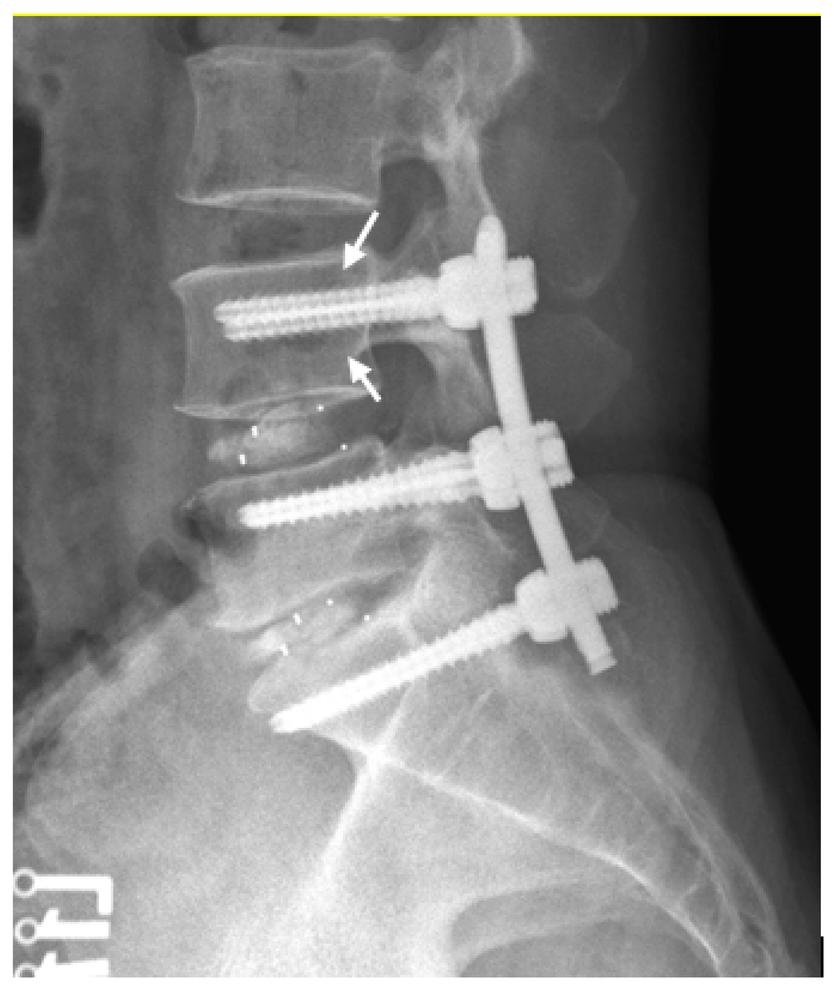

PEDICLE SCREW FIXATION

Indications

Internalthoracolumbarspinestabilisation

Standardprocedureforfractures,tumours,andmalunions Burstfractures,vertebralcompressivefracture

Degenerativedisease(spondylolisthesis,discherniation, spinalstenosis)

Steps

Cortex Opening: Performed at respective entry points with a burr/rongeur Visualise cancellous bone of pedicle, advancing further with drill, gearshift, probe. The screw shouldtraverse80%ofthevertebralbody

2 Medio-lateral inclination: Rotate to avoid medial penetration of spinal canal or anterior penetration of vertebral body cortex Screws should converge but remainentirelywithinpediclesandbody

Cranial-Caudal Angulation: Pedicle probe to navigate down isthmus into vertebral body; Aim for contralateral transverse process to ensure parallelism with superior endplate At L1, horizontal angulation is 10-15 degrees but increasesby5degreesatlowerlevels

3 Screw Insertion: Pedicle sounding device with ball tip to palpate and confirm trajectory is complete. No breaches in pedicle wall apart from main trajectory should be detected A screw (monoaxial or polyaxial) of the right diameter measured by the device is inserted into the samepath.

Depthcorrelateswithpulloutresistance,buttrade-off presentwithrisks(eg anteriorcortexrupture) Aimfor 80%pediclescrewinsertiontoprovidesafeandsufficient pulloutresistance

Morestraightforwardtrajectoriesandgreater convergencecanincreasepulloutresistance Pilotholetappingpriorscrewinsertionensurescorrect screwtrajectoryandensuresstabilityinpediclewalls Avoidoverdoing,whichmayweakentheimplant-bone interface

Undertapby1mm Avoidcreatingapilotholewiththe samesizescrew

FluoroscopyguidanceandRoboticarmsurgeryhave beendemonstratedtosignificantlyimproveaccuracy withreal-timeimaging,howeveratthecostofradiation exposureandlimitationswith2Dviews,on2planes

Benefits

Pedicleisthestrongestpartofposteriorspine-allowsfor stabilityandothercorrectiveprocedures(egderotation, translation) Canstable3columnsofDenis

Doesnotrequireintactlaminae,facetjointsorspinous processes

Providesappropriatereduction, adequatestabilisation,rapid spinalcorddecompressionandrapidimprovementin mobility

Fastrestorationofsagittal/coronalalignmentinkyphotic fractures

Limitations

Commonly results in late-onset discomfort/pain due to pseudoarthrosisorscrew-relatedissues

May cause nerve root irritation, superficial and deep wound infections

Misplacement,poorpositioningandbreachesarecommon

11 A B C D

Figure7:IllustrationofPedicleScrewFixation A) Entry Points, B) Cranial-CaudalAngulation,C)Medio-LateralInclination,D)Screw Insertion